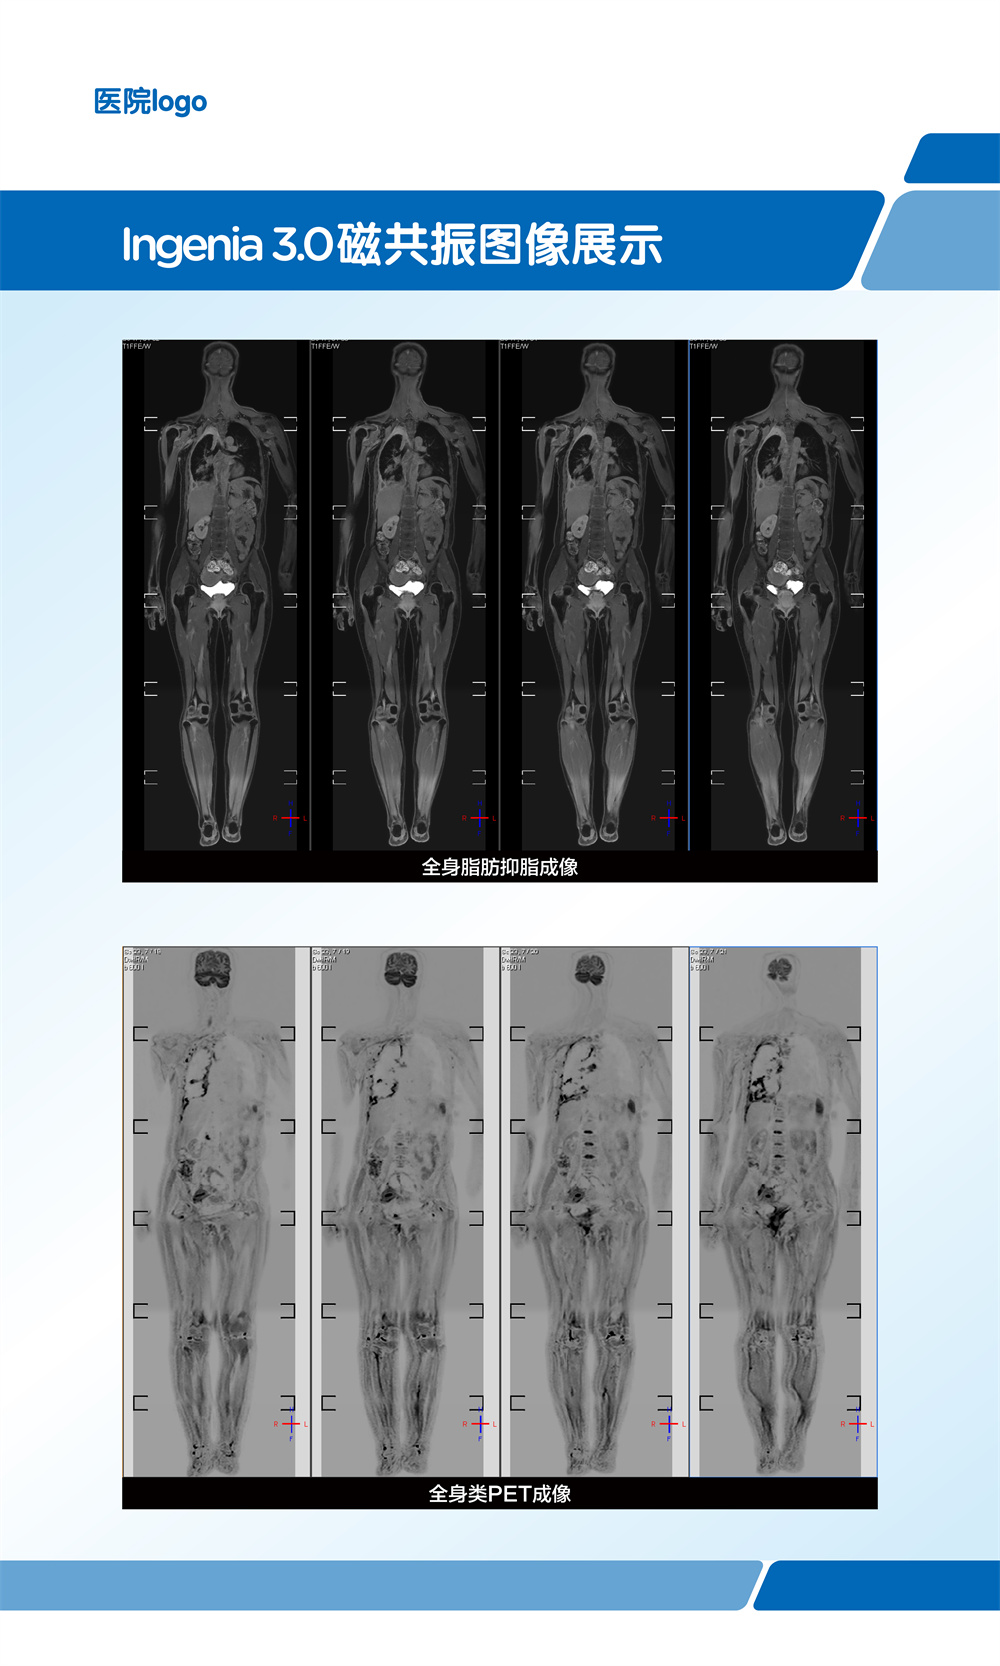

在全身弥散加权成像的同时,可进行磁共振全身扫描,增加肿瘤检出敏感性。

临床应用范围:寻找恶性肿瘤原发灶;恶性肿瘤分期;全身转移灶筛查;淋巴结转移筛查;术后放化疗疗效监测;恶性血液肿瘤疗效观察;体检与肿瘤筛查。